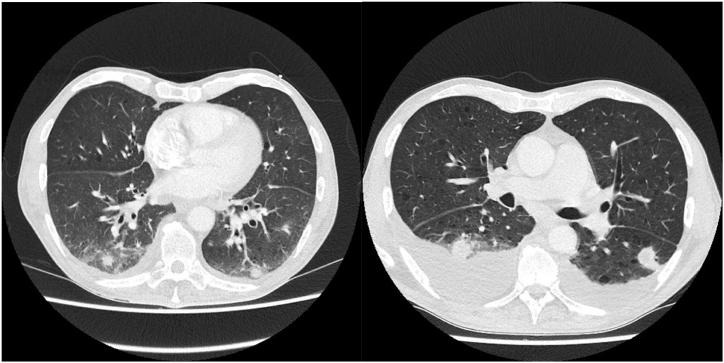

Tularemia is a rare zoonotic disease caused by the two predominant subspecies of Francisella tularensis, namely subspecies tularensis and subspecies holarctica. The latter is less virulent than the former, is endemic in Europe, and usually has a mild disease course, although respiratory involvement and bacteraemia can occur. Tularemia in Belgium is rare, but the incidence seems to be increasing. It therefore seems prudent to raise awareness among clinicians for this potentially severe disease. We report the first case of pneumonic tularemia with bacteraemia from Belgium, and want to recommend including Francisella tularensis in the differential diagnosis of pneumonia when an unfavorable evolution is seen with standard treatment.

兔热病是一种罕见的人畜共患病,由土拉弗朗西斯菌的两个主要亚种引起,即土拉弗朗西斯菌亚种和全北区亚种。后者的毒力低于前者,在欧洲呈地方性流行,通常病程较轻,尽管可出现肺部受累和菌血症。兔热病在比利时较为罕见,但发病率似乎在上升。因此,提高临床医生对这种潜在严重疾病的认识似乎是明智的。我们报告了比利时首例伴有菌血症的肺型兔热病病例,并建议在标准治疗效果不佳时,将土拉弗朗西斯菌纳入肺炎的鉴别诊断。